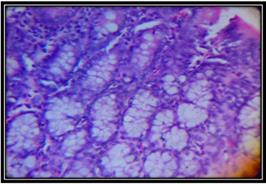

Histopathological view of the colon

Histopathology of the colon of all groups were studied and reported in [fig. 6] to [fig. 10]. Etoricoxib and atorva stastin treated groups showed that decrease in hyperplasia and dysplasia. DMH with Atorvastatin and Etoricoxib group revealed that there was marked regression in inflammation and moderate reduction in hyperplasia in animals.

Fig. 6: Normal control group

Fig. 7: DMH control group

Also results showed that the decrease in the level of SOD in DMH control animals (9.45 units/mg of protein) whereas, the group treated with combination showed significantly increased levels of SOD (17.71 units/mg of protein) as compared to level of SOD found in Etoricoxib (13.68 units/mg of protein) and Atorvastatin single drug treated groups (11.24 units/mg of protein). The level of CAT was found to be markedly decreased in DMH control animals (18.94 units/mg of protein) however, the group received combination showed increased level of CAT (41.42 units/mg of protein) as compared to levels observed in groups received individual drug treatments of Etoricoxib (29.31 units/mg of protein) and Atorvastatin (34.69 units/mg of protein). Morphological view of the colon showed that the appearance of multiple plaque lesions (MPLs). MPLs were recognized as either raised or non-raised lesions with identifiable tissue growth in carcinogen treated animals. The colon of DMH control animal showed highest occurrence of MPLs than the occurrence of MPLs in colon of Etoricoxib and Atorvastatin alone treated animals while there was still less number of MPLs found on colon of animals received combination of Etoricoxib and Atorvastatin. Observations of histopathological study indicated that there was marked dysplasia and hyperplasia in DMH control animals. The crypts were found to be enlarged along with distinct inflammatory changes. While animals received Etoricoxib alone showed decrease in hyperplasia and dysplasia indicated its efficacy as a chemo preventive agent. Histopathological results revealed that there was marked regression in inflammation and moderate reduction in hyperplasia in animals treated with combination of Etoricoxib and Atorvastatin. Also the size and shape of the cells were found to be nearly uniform with reduction in occurrence of aberrant crypt foci.